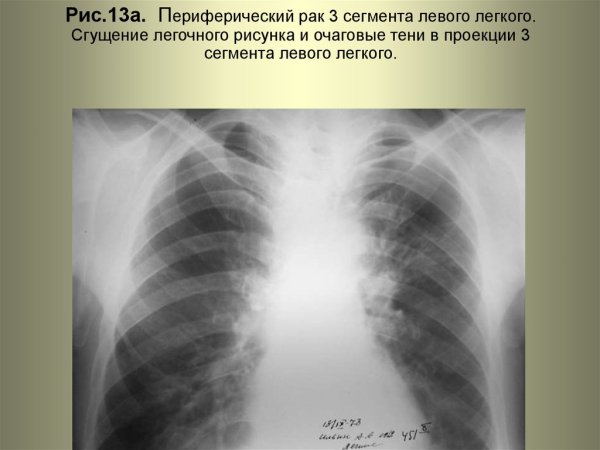

Сгущение легочного рисунка - это патологическое состояние, характеризующееся увеличением толщины или интенсивности легочных тканей на рентгеновских снимках. Обычно такое сгущение свидетельствует о наличии воспалительных процессов, инфекций, опухолей или других заболеваний в легких. Диагностика и дальнейшее лечение требуют индивидуального подхода к каждому пациенту, поэтому важно обратиться к квалифицированному врачу для получения точного диагноза и назначения соответствующего лечения.